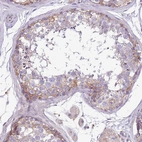

Immunohistochemical staining of human placenta shows moderate to strong membranous positivity in decidual cells.